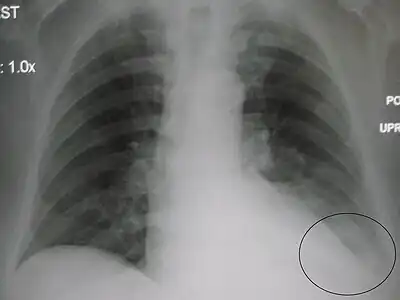

AP CXR showing left lower lobe pneumonia associated with a small left sided pleural effusion

Left upper lobe pneumonia with a small pleural effusion.